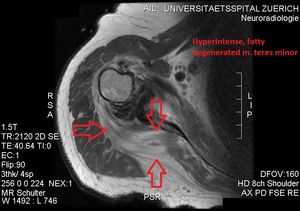

초음파검사는 작은원근의 지방 퇴행성 위축을 탐지하는 데 사용되며, 손상된 근육에서 에코 발생이 증가하고 근육 부피가 약간 감소하는 것을 볼 수 있다. 자기 공명 영상(MRI)는 신경성 근위축 진단에 유용하다. 외상 후 세포외수종은 신경 손상을 일으키며, MRI T2 강조 영상에서 신호 강도가 증가하고 T1 강조 영상에서는 정상 신호 강도를 보인다. 후방상완골선회동맥 압축과 스트레스를 유발하는 팔의 위치나 조작으로 인한 혈류 감소는 도플러 초음파 검사로 진단할 수 있다. 혈관 옆 신경이 탐지된다. 팔을 들어올린 자세에서는 액와신경혈관다발이 삼각근을 관통하기 직전 후방 겨드랑 주름에서 보이지만, 팔을 내린 자세에서는 후방 코스가 잘 보인다. 동맥의 자세한 진단을 위해서는 MR 혈관 조영술이 필요하다. 초음파 검사는 무게를 갖는 공간을 탐지한다. 근전도 검사는 신경 전도 속도 감소와 관련 근육의 신경 제거 상태를 밝혀내는 데 유용하다.[4][5]

소원근 위축은 회전근개 파열의 결과로 발생하지만, 단독적인 소원근 위축도 발견된다. 사변공증후군(quadrangular space syndrome)은 해부학적 터널을 지나는 구조물에 과도하거나 만성적인 압박을 유발한다. 액와신경과 후상완골 회선 동맥이 사변공을 통과한다. 처음엔 어깨 통증과 팔 아래 저림(paresthesia)을 느끼고, 팔을 벌리거나(abduction), 펴거나(extension), 바깥쪽으로 돌리거나(external rotation), 머리 위로 들어올리는 동작에서 느낀다. 소원근 선택적 위축이 보이면 해당 액와신경 분지나 후방상완골선회동맥의 압축과 함께 견인된다. 섬유대(fibrous band), 관절순(glenoid labrum)의 낭종(cyst), 지방종(lipoma)이나 정맥 팽창(dilated vein)은 사변공을 병리학적으로 점령하여 병을 일으킬 수 있다. 전방어깨탈구(anterior shoulder dislocation), 상완골 경부 골절, 완신경총(brachial plexus) 부상, 흉곽출입구증후군(thoracic outlet and inlet syndrome)에서도 비슷한 증상이 흔하게 나타나므로, 가능한 한 완전한 감별 진단을 위해 이러한 병리를 포함하는 것이 중요하다.초음파검사(ultrasonography)는 소원근의 지방 퇴행성 위축을 탐지하는 도구이며, 다친 근육의 에코 발생(echogenicity)가 늘어나고 근육 부피의 약간의 감소가 보이기도 한다. 자기 공명 영상(MRI)는 신경성 근위축(neurogenic muscle atrophy) 진단에 유용하다. 외상 후 세포외수종(extracellular edema)은 신경 손상을 일으키며, MRI T2 강조 영상(T2-weighted MRI) 결과에서의 신호 강도(signal intensity) 증가와 T1 강조 영상 결과물에서의 신호 강도 정상을 보인다. 후방상완골선회동맥 압축과 스트레스를 유발하는 팔 위치나 조작으로 인한 혈류 감소는 도플러 초음파 검사(Doppler ultrasonography)로 진단할 수 있다. 혈관 옆 신경이 탐지된다. 팔을 들어올린 자세에서는, 액와신경혈관다발(axillary neurovascular bundle)이 삼각근을 관통하기 바로 직전에 후방 겨드랑 주름(posterior axillary fold)에서 보일 수 있지만, 팔을 내린 자세에서는 후방 코스(posterior course)가 잘 보인다. 동맥의 자세한 진단을 위하여, MR 혈관 조영술(MR angiography)이 필요하다. 초음파 검사는 무게를 갖는 공간을 탐지하는 것이다. 추가적인 근전도 검사(electromyography)는 신경 전도(nerve conduction) 속도 감소와 관련 근육의 신경 제거(denervation) 상태를 밝혀내는 데 유용하다.[12][6]